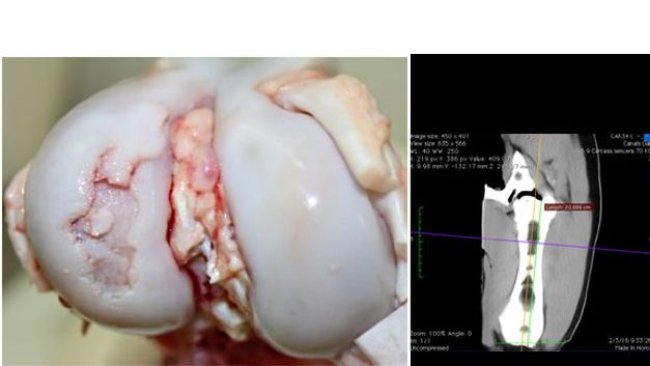

En marzo de 2021, apareció un alto porcentaje de cojeras severas en lechones de 12/17 días de edad, aproximadamente el 20% de los lechones presentes

El presente artículo revisa el efecto de componentes de la dieta sobre el hueso y la osteocondrosis, principal causa de cojeras y motivo de eliminación de reproductoras jóvenes. Por lo tanto, conceptos importantes a tener en cuenta en las dietas para recría de nulíparas.

¿Una elevada velocidad de crecimiento realmente aumenta el riesgo de osteocondrosis y cojeras?